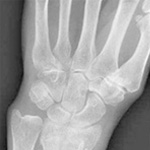

Foot and Ankle

聖マリアンナ医科大学科学講座の足の外科の歴史は故三好邦達初代主任教授の時代から始まります。三好教授は先天性内反足をはじめとする足の外科領域の診療、研究に力を注ぎ「日本足の外科研究会」を発足されました。昭和51年に第1回の会長を務められ、その後に名称を「日本足の外科学会・学術集会」とし平成9年に青木治人第2代主任教授が第22回を開催されました。・・・